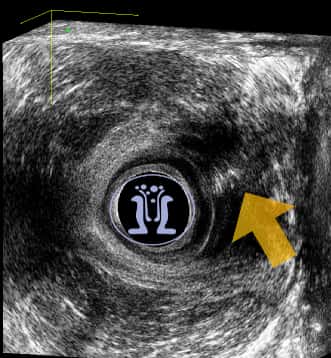

Γυναίκα ασθενής 31 ετών προσέρχεται με φλεγμονή στο δεξί μεγάλο χείλος του αιδοίου από μηνός. Στο ιστορικό της αναφέρει εγχείρηση για βαρθολίνειο δεξιά προ διετίας. Κλινικά ανευρίκεται δερματικό στόμιο δεξιά κοντά στο κόλπο και η εξετάστική μήλη διεισδύει σε ενα μεγάλο βάθος. Υπερηχοτομογραφικά ανευρίσκεται επικοινωνία με το έντερο που συμπεριλαμβάνει όλο το μήκος του σφιγκτήρα στην 12η ώρα.